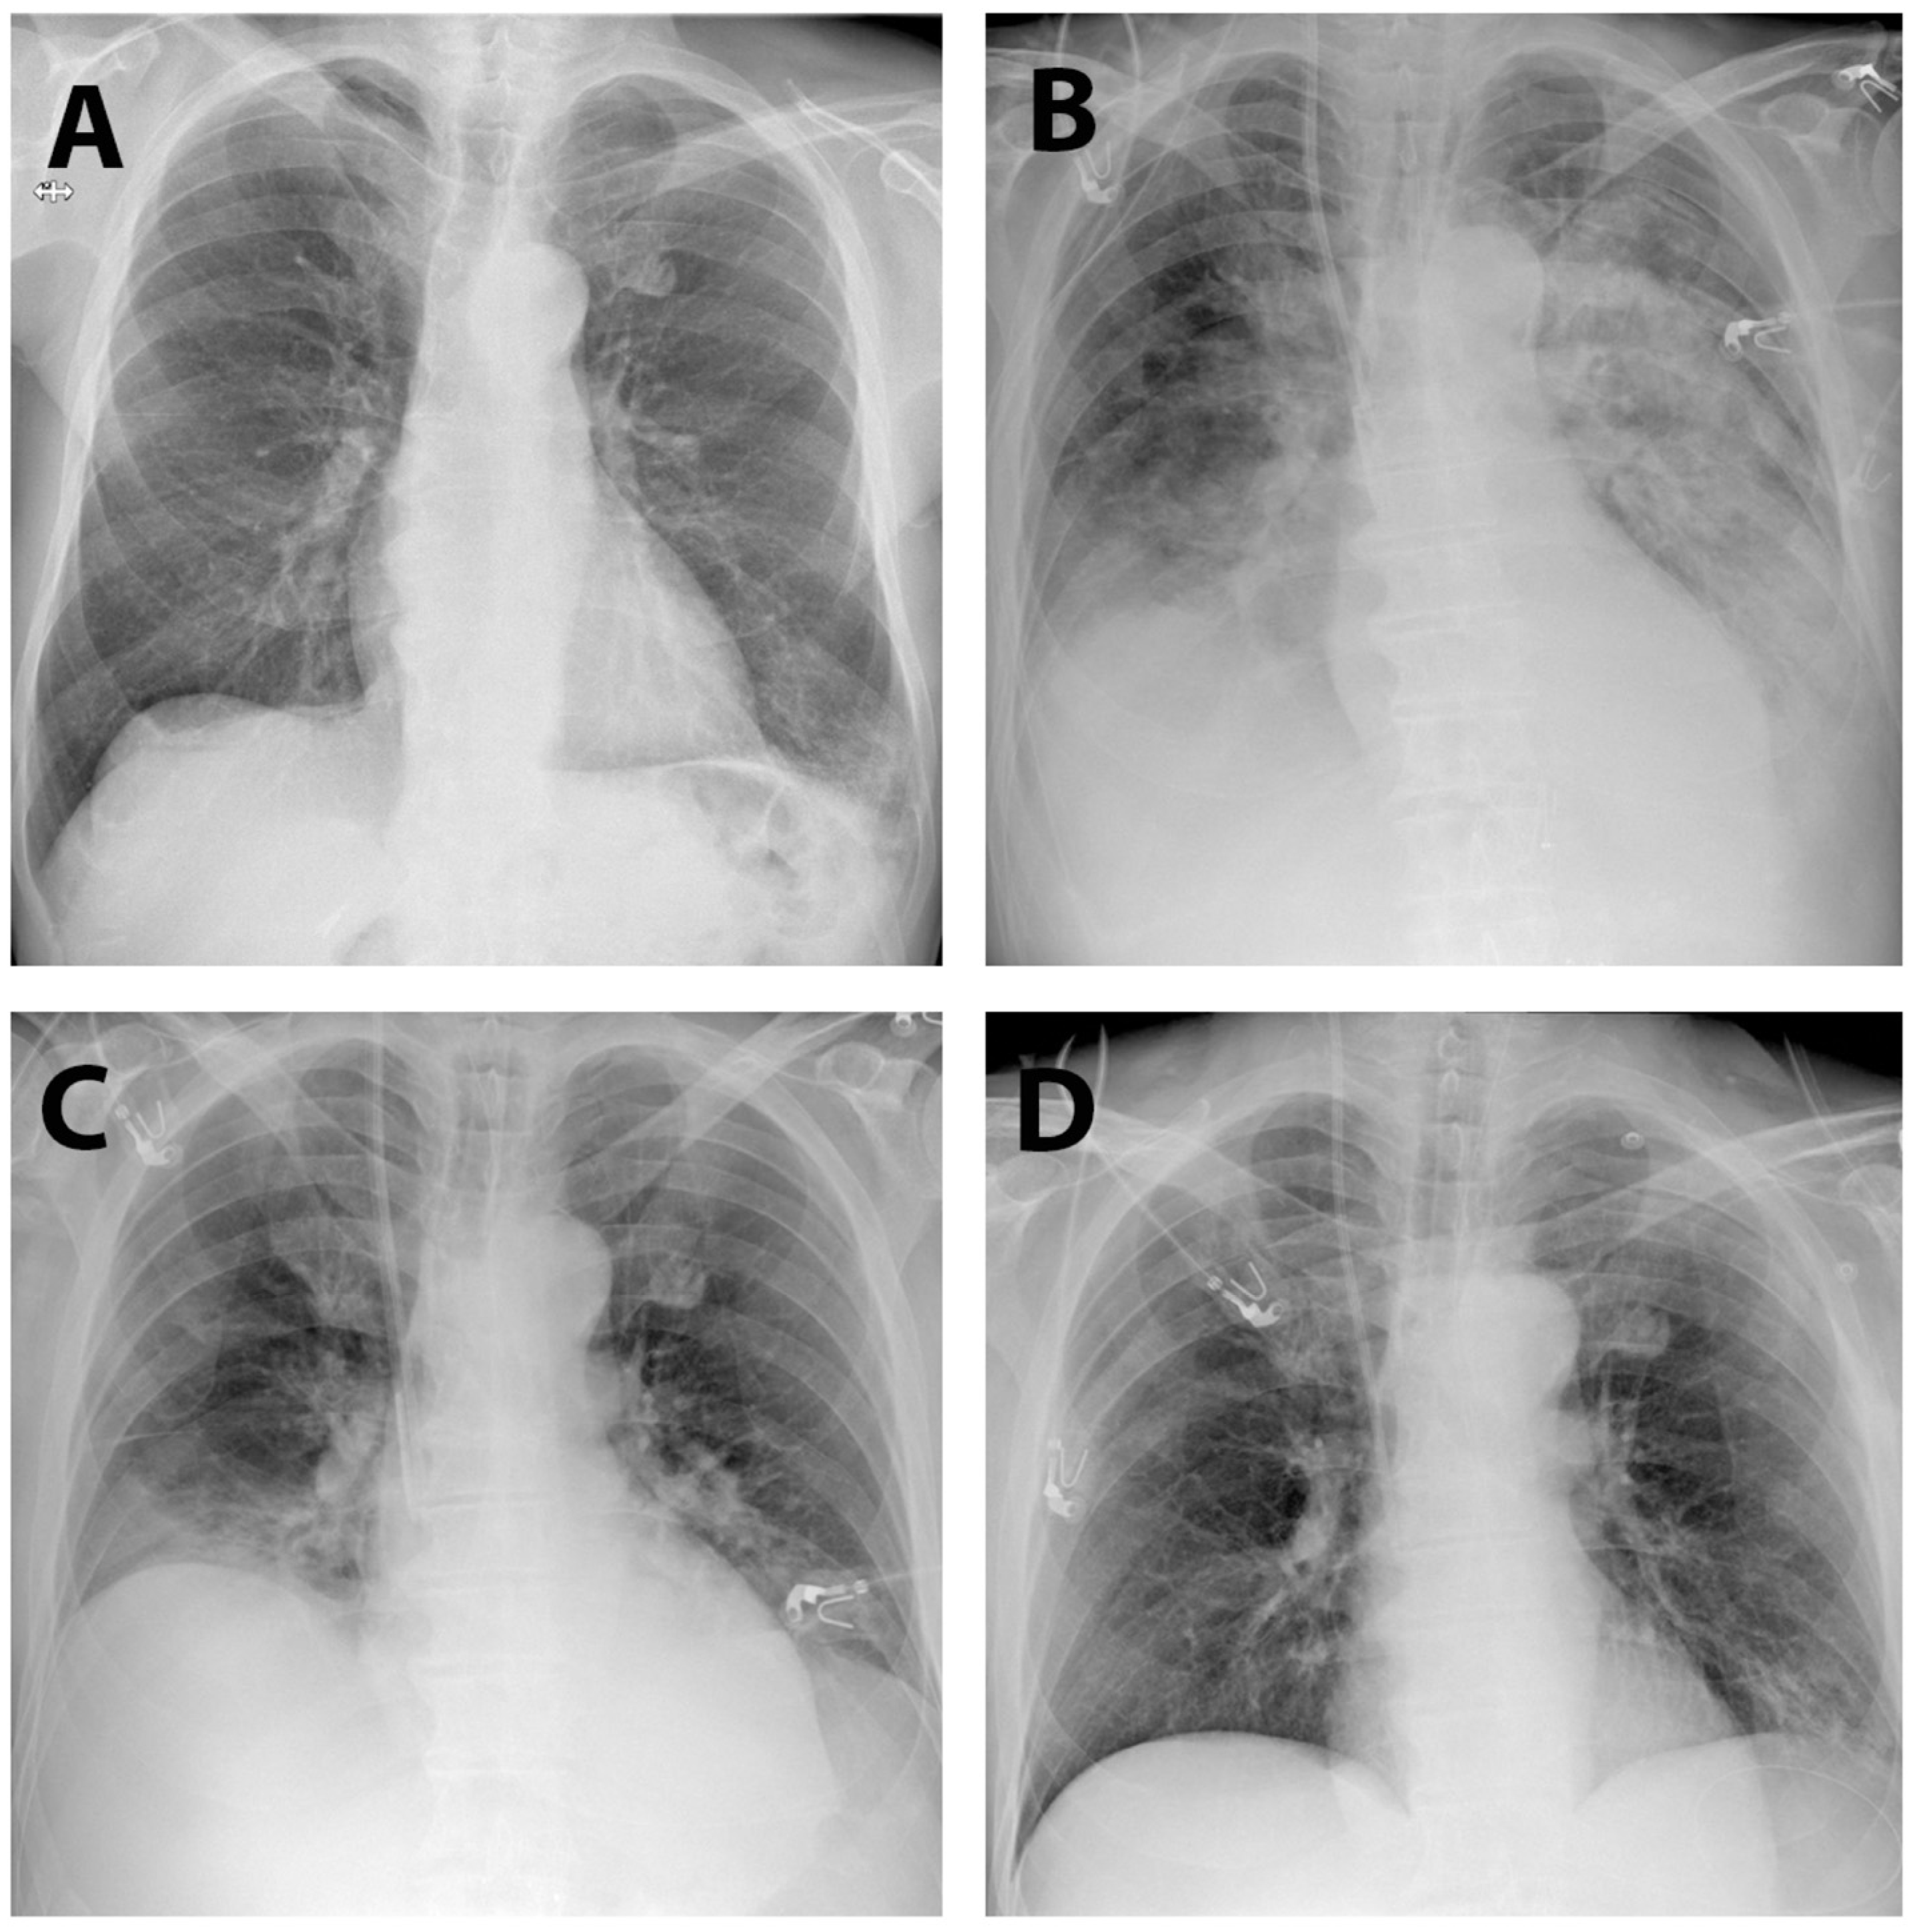

2. Case Report